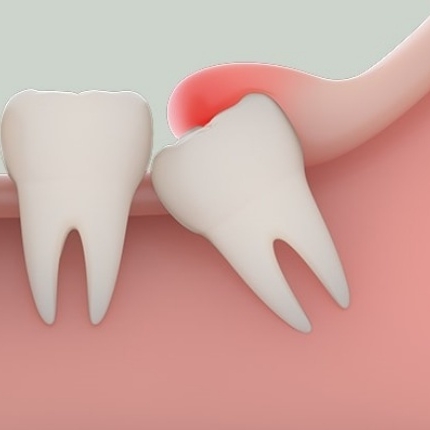

Răng khôn mọc lệch 45 độ chèn vào những răng bên cạnh

Với những răng khôn mọc thẳng có thể hỗ trợ thêm cho quá trình ăn nhai của con người. Tuy nhiên, các răng này lại thường mọc lệch do những cản trở tại chỗ, gây xô đẩy răng toàn hàm. Không chỉ vậy, vì mọc trong cùng, răng khôn thường dễ khiến dắt thức ăn, vi khuẩn gây nên tình trạng sâu răng hoặc viêm nhiễm. Do đó các bác sĩ nha khoa thường khuyên nhổ bỏ nếu thể trạng bạn đạt yêu cầu.

Răng mọc lệch, xô đẩy, ảnh hưởng tới những răng khác;

Răng mọc ngang, mọc ngược, bị lợi trùm gây sưng tấy, đau nhức;